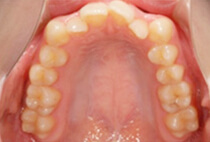

前歯のガタガタを気にして来院されました。なるべく抜かずに、短い治療期間で矯正治療を終わらせる治療をご希望されました。スピード矯正治療で、なるべく早期に前歯の審美性を改善することにしました。

コルチコトミー(スピード矯正処置)後1ヶ月の様子です。

上顎のみの舌側矯正治療ですが、下の歯には治療後半の噛み合わせを調節する段階で装置をセットしました。コルチコトミーを行ったことで、1ヶ月後には前歯のガタガタが大幅に改善できました。また、治療期間の短縮でけでなく、非抜歯できれいな歯並びに治療できました。